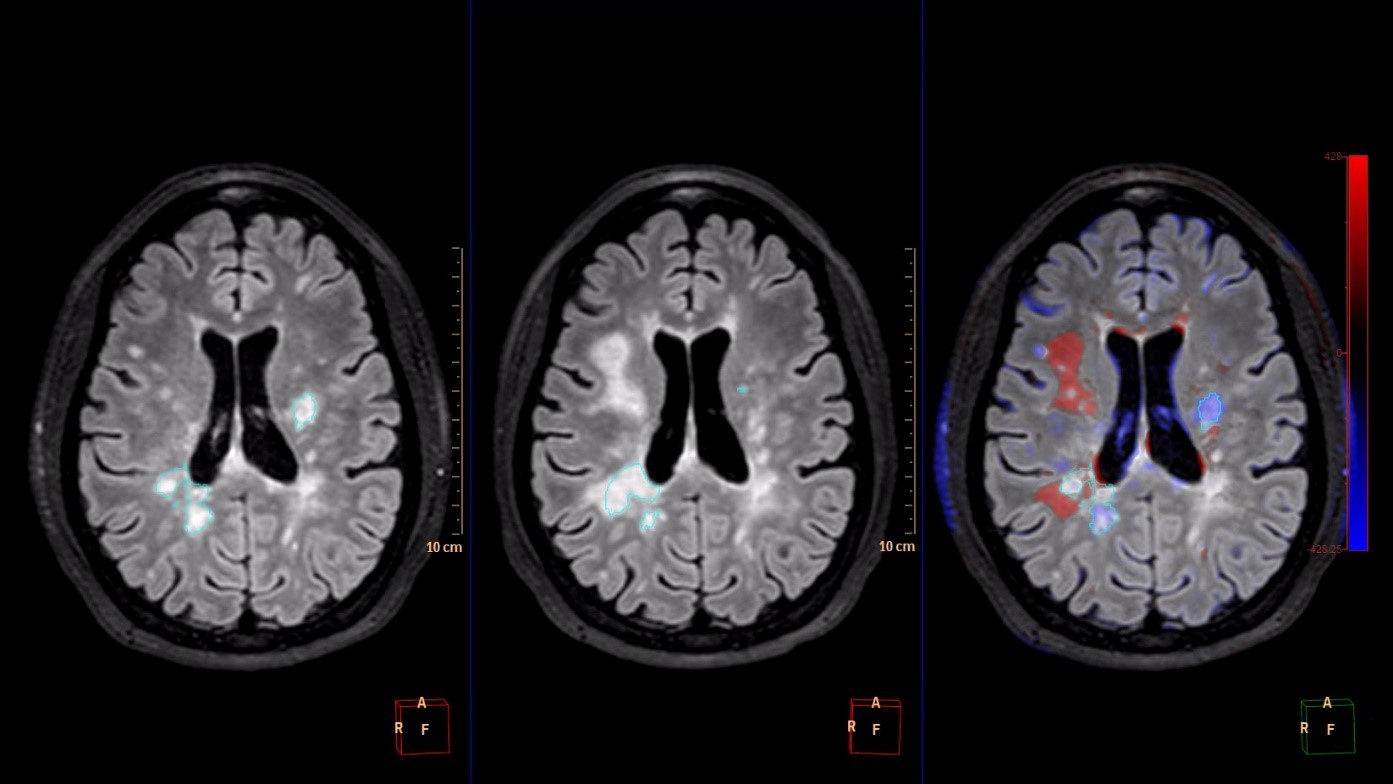

IntelliSpace Portal 9.0 offers Longitudinal Brain Imaging (LoBI), an application to help clinicians visualize subtle differences in the brain images of the same individual across time, which may be used by clinicians as the assessment of neurological disease progression. Multiple images are automatically aligned and registered to simplify comparison, and the application provides editing tools and volumetric quantification. Comparative Brain Imaging (CoBi) functionality even allows users to track subtle differences in the brain by subtracting scans taken at different points in time.